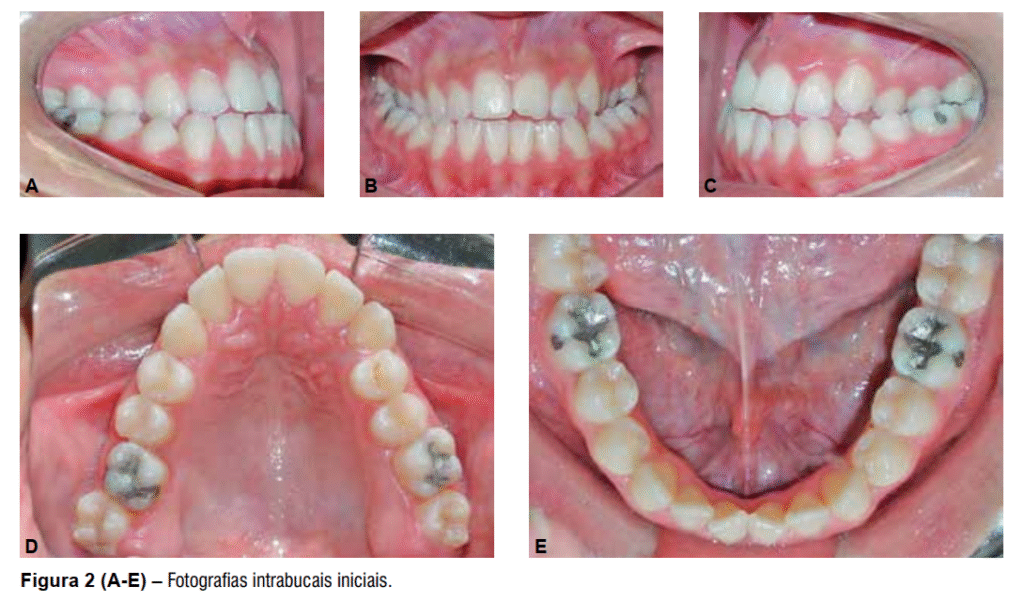

A paciente F.A.A. de 12 anos de idade apresentava um perfil suavemente convexo e padrão facial vertical (Figura 1 A-B), má oclusão de Classe III completa bilateral, mordida cruzada (exceto dos segundos molares) e mordida aberta anterior (Figura 2 A-E).